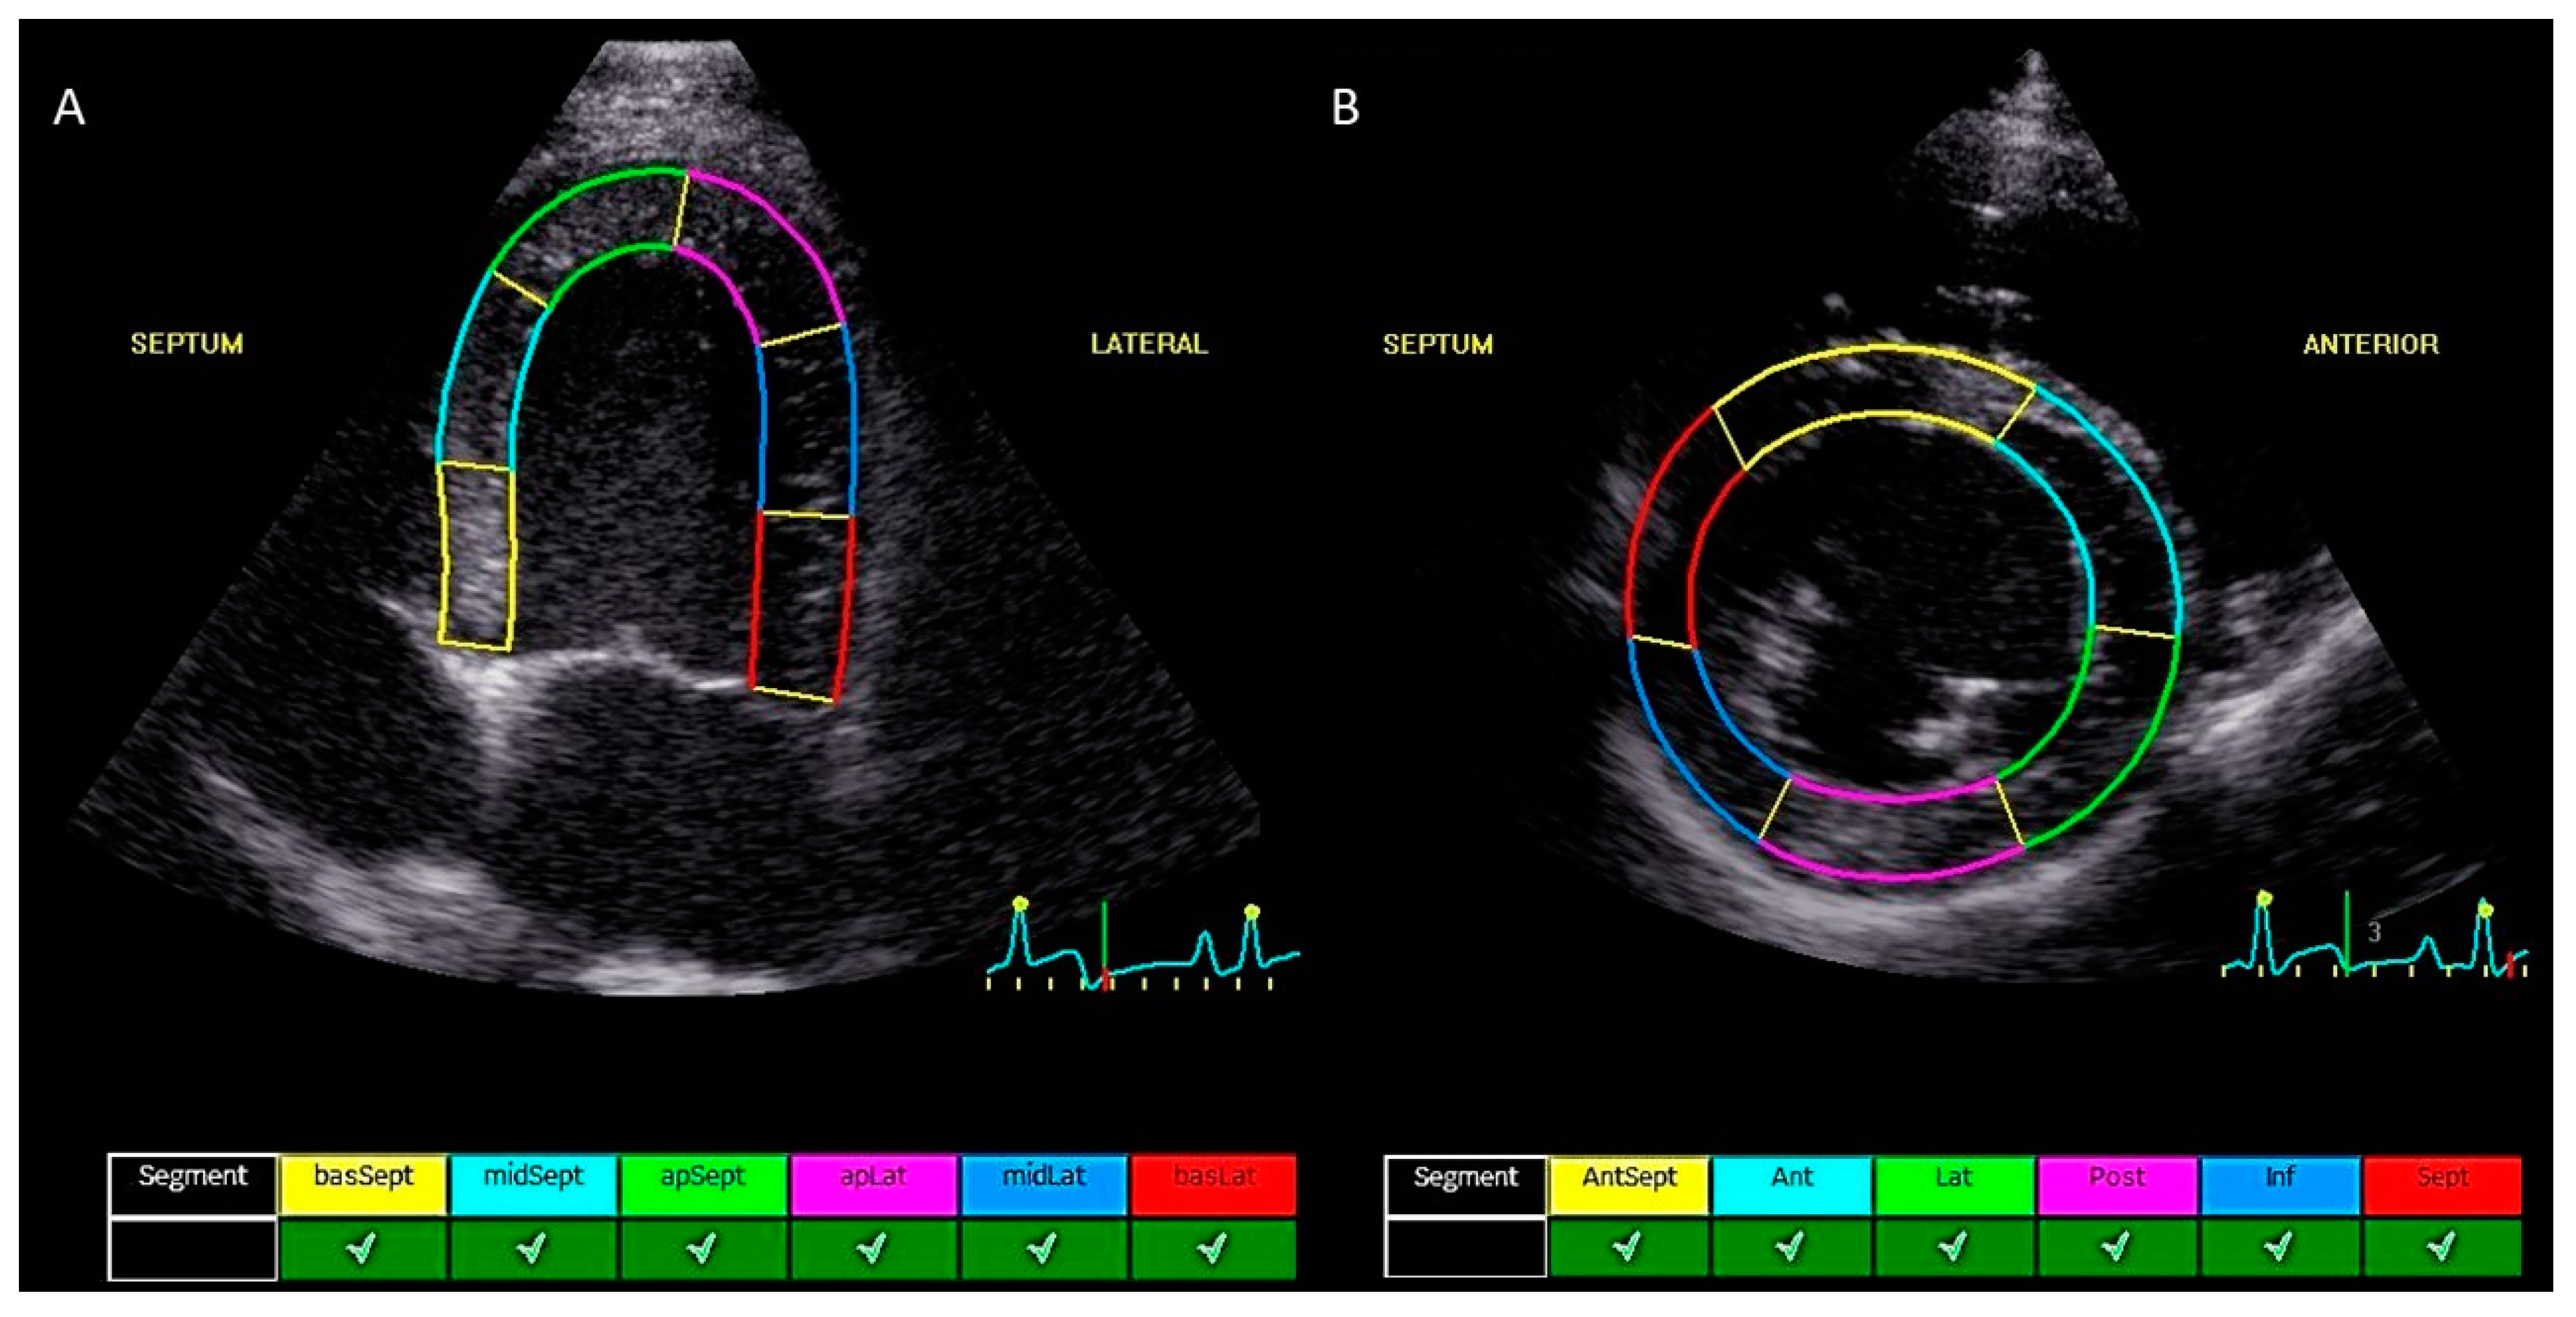

2.2. Echocardiographic Measurements